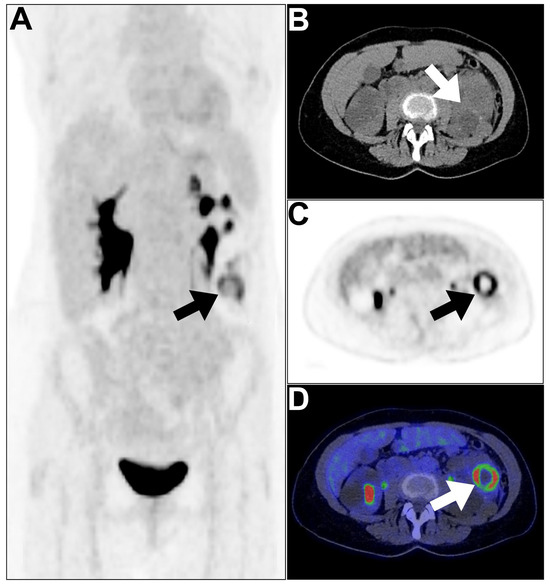

- Zhou, Y.; Yang, X.; Liu, H.; Luo, W.; Liu, H.; Lv, T.; Wang, J.; Qin, J.; Ou, S.; Chen, Y. Value of [68 Ga] Ga-FAPI-04 imaging in the diagnosis of renal fibrosis. Eur. J. Nucl. Med. Mol. Imaging 2021, 48, 3493–3501. [Google Scholar] [CrossRef] [PubMed]

- Conen, P.; Pennetta, F.; Dendl, K.; Hertel, F.; Vogg, A.; Haberkorn, U.; Giesel, F.L.; Mottaghy, F.M. [68 Ga] Ga-FAPI uptake correlates with the state of chronic kidney disease. Eur. J. Nucl. Med. Mol. Imaging 2022, 49, 3365–3372. [Google Scholar] [CrossRef] [PubMed]

- Civan, C.; Kuyumcu, S.; Simsek, D.H.; Sanli, O.; Isik, E.G.; Ozkan, Z.G.; Hurdogan, O.; Sanli, Y. The role of [68 Ga] Ga-FAPI-04 PET/CT in renal cell carcinoma: A preliminary study. Eur. J. Nucl. Med. Mol. Imaging 2024, 51, 852–861. [Google Scholar] [CrossRef] [PubMed]